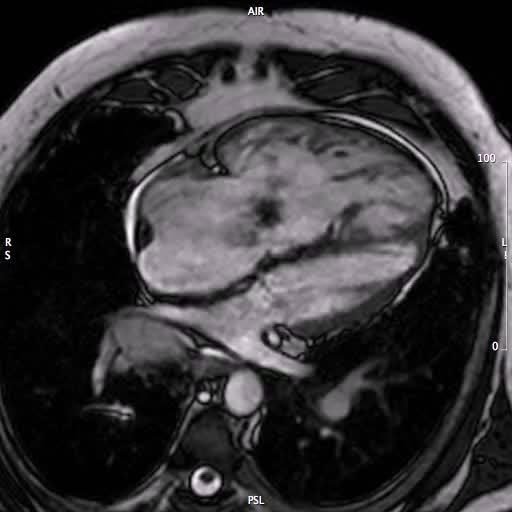

ITR e ipertensione polmonare

Santo Dellegrottaglie